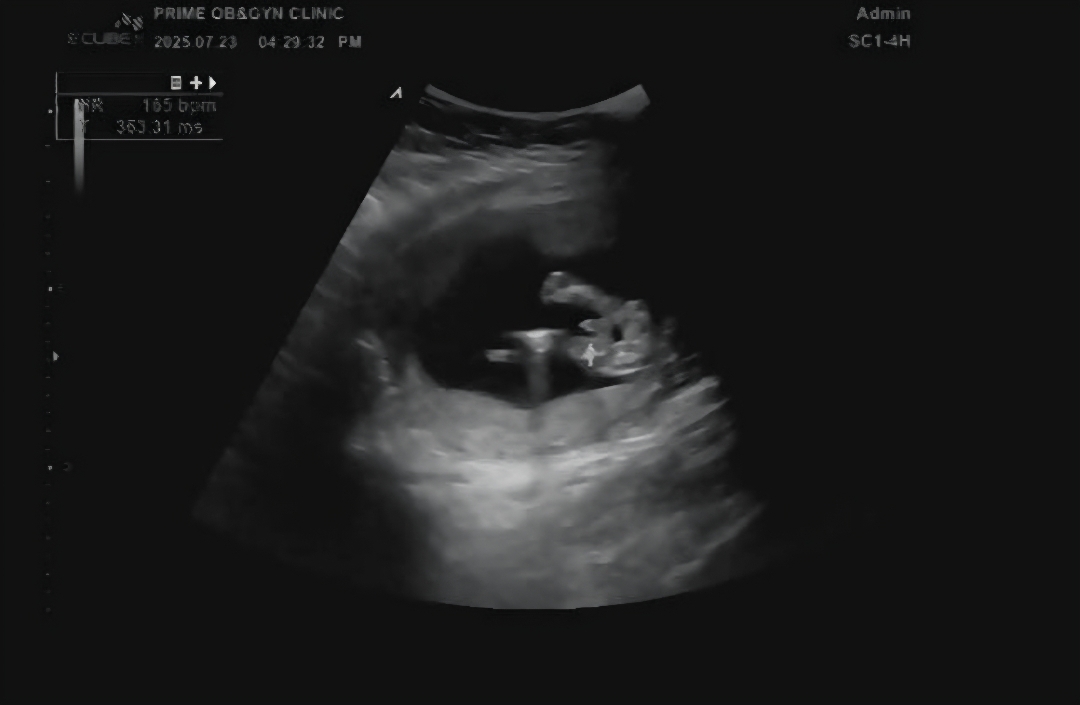

지금까지 딸인줄 알았는데 오늘 촘파보는데 아들 같아요ㅋㅋ 여러분들은 어떻게 보이시나요??